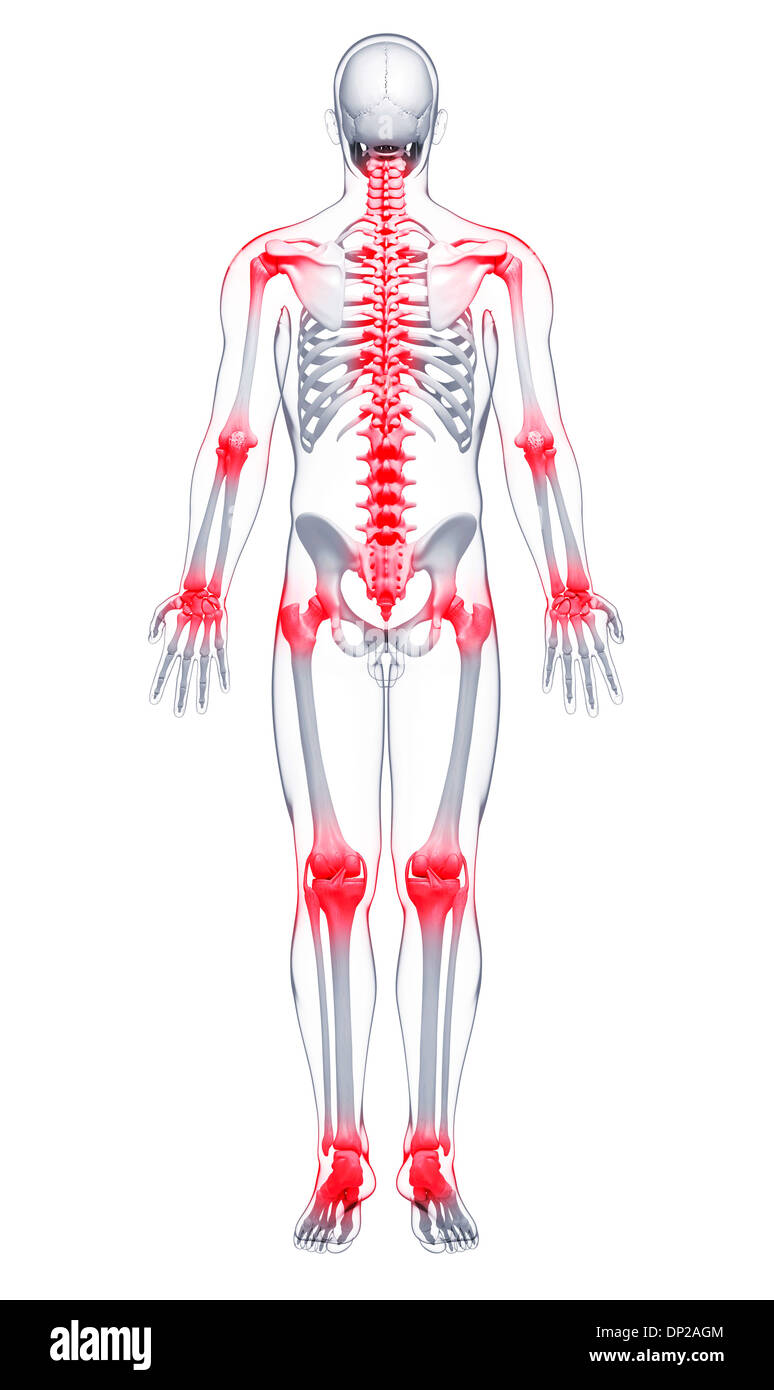

La douleur commune, artwork Banque D'Imageshttps://www.alamyimages.fr/image-license-details/?v=1https://www.alamyimages.fr/la-douleur-commune-artwork-image65205748.html

La douleur commune, artwork Banque D'Imageshttps://www.alamyimages.fr/image-license-details/?v=1https://www.alamyimages.fr/la-douleur-commune-artwork-image65205748.htmlRFDP2AGM–La douleur commune, artwork